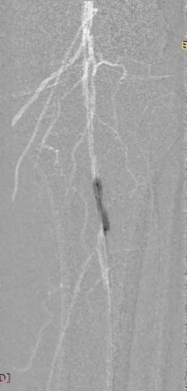

对于长段、严重钙化的股浅动脉病变,

巧克力球囊并不能完全避免夹层的发生

长段(≥20cm)、严重钙化(钙化评分≥3 分)的股浅动脉病变,因钙化范围广、质地坚硬且常伴随血管迂曲,巧克力球囊虽能降低夹层风险,但无法完全避免 —— 核心原因在于病变本身的复杂性与器械技术边界,临床需通过 “联合策略” 进一步提升安全性与疗效。

Chocolate 5-120mm

巧克力球囊扩张后

出现的夹层